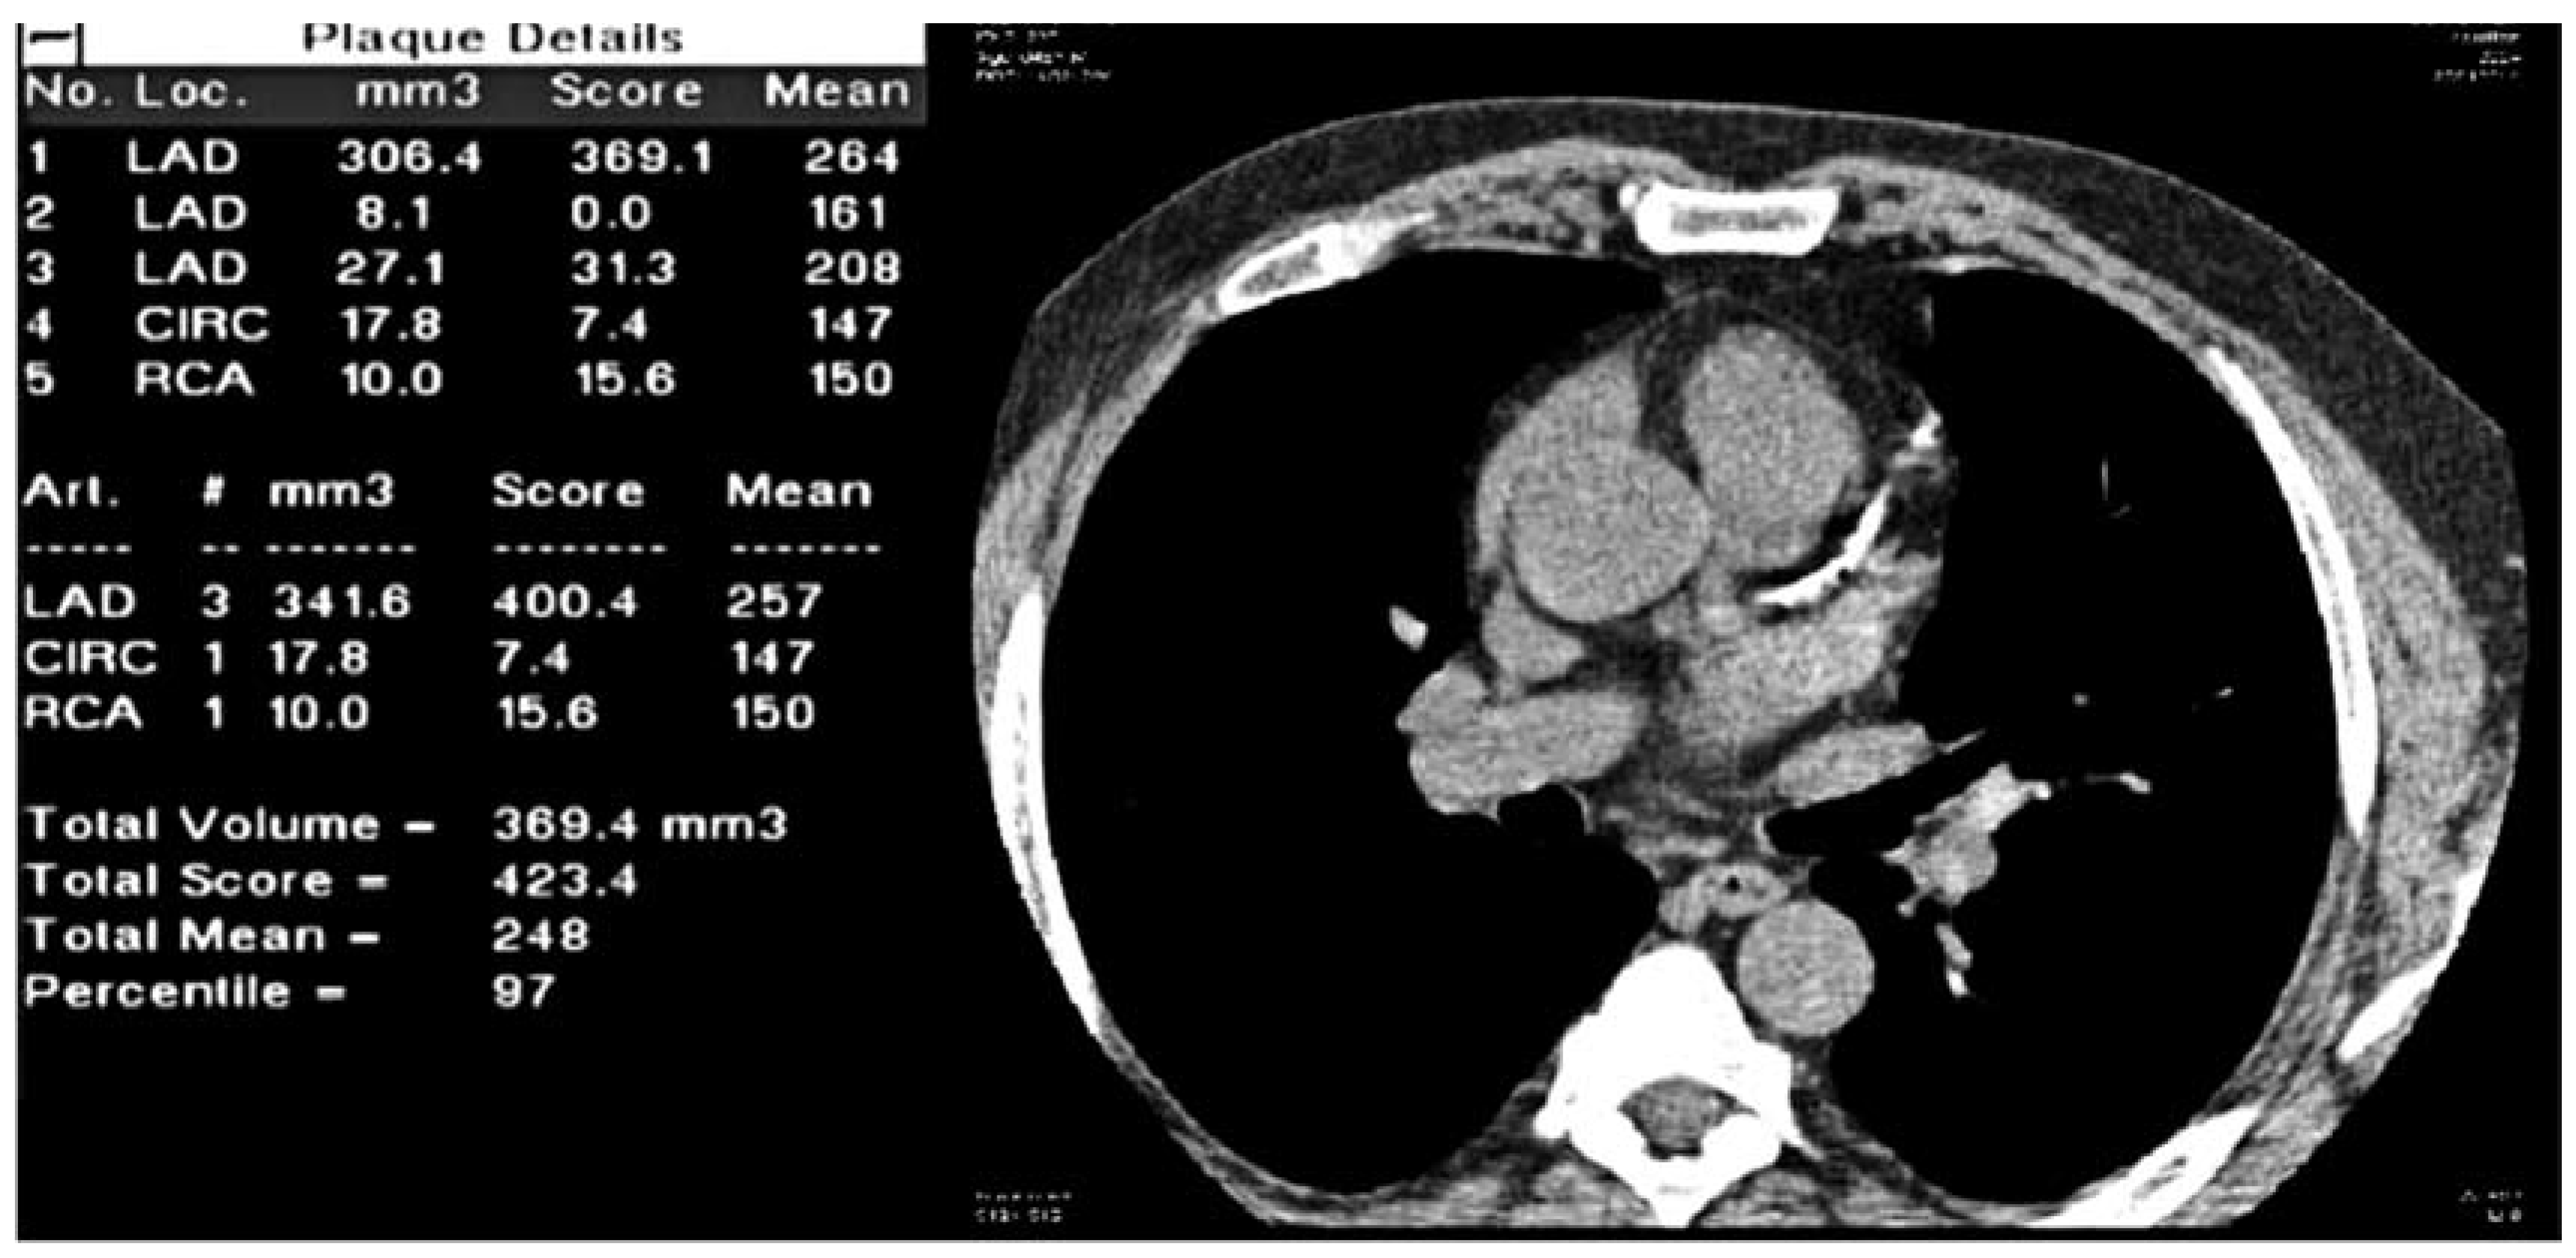

Imaging method and risk assessment using coronary calcifications (CS%)

Visualisation of coronary calcifications by cardiac gated computed tomography allows to measure the total calcified plaque burden in the coronary arteries. By using the Agatston method, which quantifies coronary calcifications based on plaque area and plaque density, a score was derived (Agatston score). Coronary calcifications were made visible for further processing by using a single-breath hold, multislice (Aquilion, Toshiba, Japan) ECG-gated, non-contrast enhanced, low-radiation scan sequence. Data were processed by using the NetraMD Software (ScImage Palo Alto, California, USA), which provides reproducible data on total Agatston calcium scores, percentile of Agatston scores, and plaque volumes for all coronary arteries and total plaque volume. The cut-off point to define that a plaque is calcified was set at 130 Hounsfield units (Figure 3).

Figure 3. Qualitative and quantitative display of coronary calcifications using images obtained from a four slice MSCT scanner and quantification software from ScImage.Inc (fda approved).